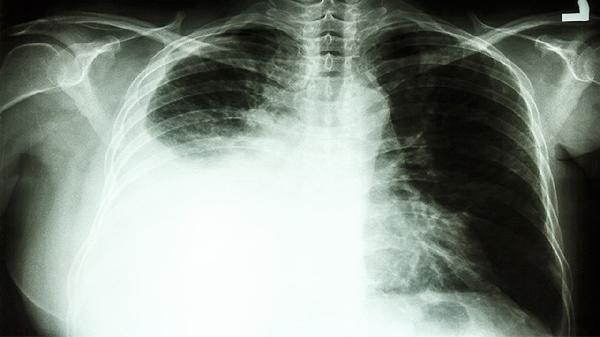

左下肺叶肺炎可能引发局限性胸痛,伴随发热、咳黄痰。肺炎链球菌感染常见,可通过胸片和痰培养确诊。轻症口服阿莫西林克拉维酸钾,重症需静脉用哌拉西林他唑巴坦。建议多饮水促进排痰,血氧低于93%需吸氧。

自发性气胸多见于瘦高体型青年,突发尖锐胸痛伴呼吸困难。肺组织压缩超过30%需行胸腔穿刺抽气或闭式引流。反复发作患者可能需胸膜固定术。发病后应避免乘坐飞机或潜水,戒烟可降低复发风险。